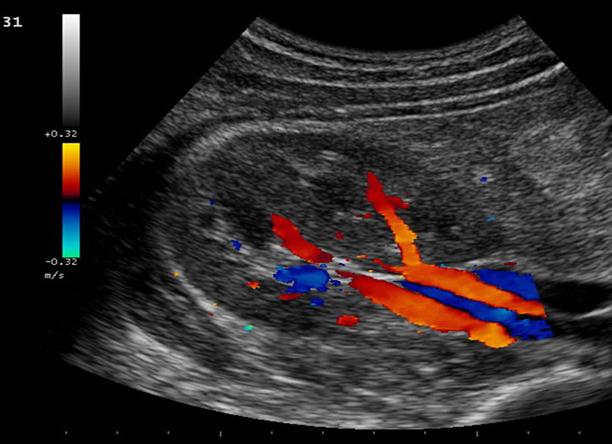

УЗИ дает, так называемую, «общую картинку», показывает строение сосудов. А УЗИ с доплером – движение крови по сосудам, ее скорость и направление. Также можно увидеть очаги, где кровоток, в силу определенных причин, заблокирован. Это позволяет принять своевременные шаги и назначить эффективное лечение.

Триплексное сканирование отличается добавлением цветного изображения, что придает исследованию дополнительную точность.

Использование УЗИ с доплером позволяет с помощью звуковых волн увидеть цветное изображение сосудов, обнаружить затруднение в кровотоке, в том числе и отложение бляшек атеросклероза.

Также стоит отметить, что допплер сосудов позволяет использовать различные цвета, чтобы увидеть, как течет кровь, где кровоток блокирован или имеет проблемы, какой является скорость и направление крови в конкретной артерии. Какие особенности имеет УЗДГ артерий? Цветовое допплеровское картирование строится на том, что применяется одновременно обычное УЗИ и допплерогарфия. Благодаря полученным результатам, можно диагностировать следующие заболевания: